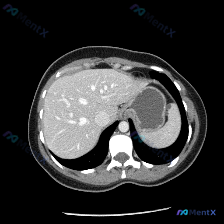

最近看到一个很有意思的影像分析场景,整理了一下思路和大家分享。 先看基础情况 用户预设了“脾脏病变”的方向,提供了一张腹部CT横断面软组织窗图像,从分析来看是增强扫描的动脉期或早期门脉期。 这张CT的核心表现 先整理一下明确的阳性/阴性信息: ✅ 图像质量:清晰度良好,无明显运动/金属伪影,软组织辨...

整理了一份很有意思的读片病例,差点被最初的提问带偏,分享一下思路: 病例背景 核心提问是“这张图里脾脏有什么病变?”,先来看影像的客观描述。 关键影像信息(增强CT横断面) 1. 扫描层面与质量:上腹部增强,对比度好,结构清。 2. 我们重点看的脾脏:边缘轮廓大致正常,未见明确局灶性低密度、高强化或...

今天看到一个挺有意思的影像分析场景:拿到一张上腹部CT横断面(软组织窗),问题直接指向“脾脏病变”,但仔细看完影像描述,我觉得这里可能藏着一个临床思维的小陷阱。先把资料理一理: --- 影像描述核心信息整理 肝脏:轮廓清晰,形态正常,肝实质密度均匀,未见明确局灶性占位,肝内血管走行自然。 脾脏:左上...

看到一个很值得讨论的场景,整理了一下思路和大家分享: --- 先看核心事实 用户预设“存在脾脏病变”,但提供的轴位腹部CT(软组织窗)影像分析结果非常明确: 1. 脾脏本身:轮廓清晰,大小正常,实质密度均匀 2. 其他腹部脏器:肝脏、胰腺(部分)、右肾均未见明显局灶性病变 3. 腹腔整体:血管走行自...

今天看到一份很有意思的腹部CT读片案例,整理一下思路和大家分享。 病例背景 用户最初的问题是「识别图中的脾脏病变」,但拿到图像(腹部CT横断面软组织窗)后,先按流程做了系统评估。 --- 影像关键信息整理 先把看到的客观情况列出来: 1. 脾脏:形态大小正常,包膜光滑,密度均匀,未见任何局灶性异常,...

最近看到一个读片资料,预设问题是“图像中是否存在脾脏病变”,先和大家理一下完整的思路。 --- 先列一下拿到的「影像客观事实」 这是一幅上腹部CT软组织窗横断面图像: 1. 肝脏:轮廓平整,实质密度均匀,肝内血管走行清晰,无受压移位; 2. 脾脏:划重点——形态正常、大小正常、实质密度均匀,未见局灶...